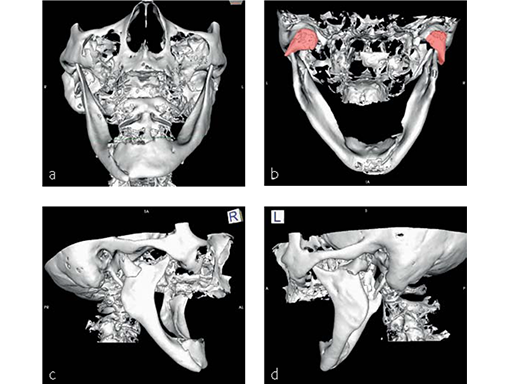

Fig 1 Preoperative 3-D CT scans:

a) Frontal view. Right anterior body fracture associated with slight widening of the mandibular arch.

b) Dorsal view. Shortening of both rami due to lateral override displacement and medial angulation of both condylar bearing fragments, partial medial dislocation out of the fossa of the right condylar head.

c) Right lateral view. Lateral override of posteriorly displaced condyle bearing fragment and decreased ramus height.

d) Left lateral view. Lateral override position and posteromedial angulation of condyle bearing fragment.